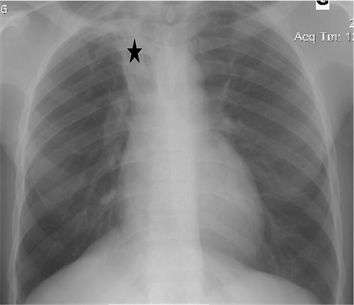

Of the 753 radiographs obtained, 712 were normal (94.55%), while 41 X-rays (5.44%) showed abnormalities (Table 2), thus 14 cases (1.85%) of blunting of left costophrenic angle, 9 cases (1.19%) bunting of right costophrenic angle, 8 cases (1.06%) of cardiomegaly, 3 cases (0.39%) of basal infiltrate, 6 cases (0.79%) of apical infiltrate and one case (0.13%) of right pleural liquid effusion of mean abundance with right para-tracheal opacity. Among these abnormalities 40 cases (5.31%) were considered sequelae and one case (0.13%) as evolutionary (Figure 2).

The figures below show the examples of sequelae (Figures 3-5) and evolutionary (Figure 6) abnormalities encountered.

Figure 5. Moderate right pleural effusion (red arrow), anterior superior right paratracheal opacity (black star) and right hilary opacity (red star).